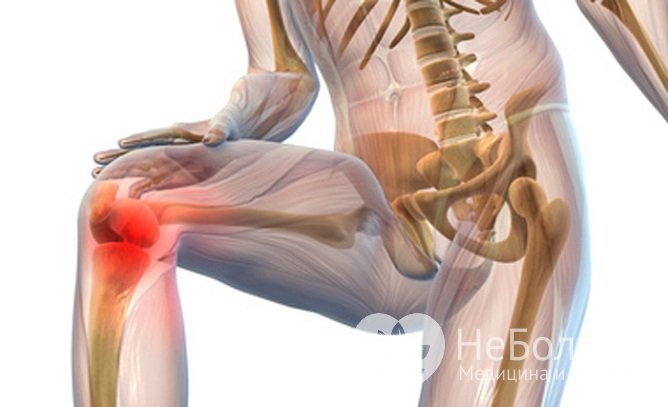

Поражение суставов при артритеПричины развития воспалительных процессов в суставах могут быть самыми разнообразными. Острое воспаление может быть вызвано травмой, инфекцией, аллергической реакцией или попаданием токсичных веществ в суставную полость при укусах змей, пауков и ядовитых насекомых. Хроническая форма часто развивается на фоне различных нарушений в работе внутренних органов и систем:

Предрасполагающим фактором артрита является пожилой возраст и наличие хронических заболеванийНередко причиной артрита оказывается постоянная микротравма суставных структур при профессиональных занятиях спортом и тяжелом физическом труде, когда имеет место интенсивная нагрузка на одни и те же группы мышц. С другой стороны, малоподвижный образ жизни также способствует развитию воспалительных процессов в суставах, особенно когда к гиподинамии примешивается злоупотребление алкоголем, несбалансированное питание и нехватка витаминов в рационе.

На ранних стадиях артрит проявляется умеренными болями и скованностью в суставахБольшинство пациентов обращается к врачу на II стадии заболевания. Постоянный дискомфорт в области суставов, появление чувствительных припухлостей, вызванных избыточной продукцией синовиальной жидкости, характерный хруст, эритема и отечность проблемных участков – явные признаки воспаления. Вынужденное положение тела и конечностей могут указывать на сильные мышечные спазмы на фоне потери подвижности суставов.